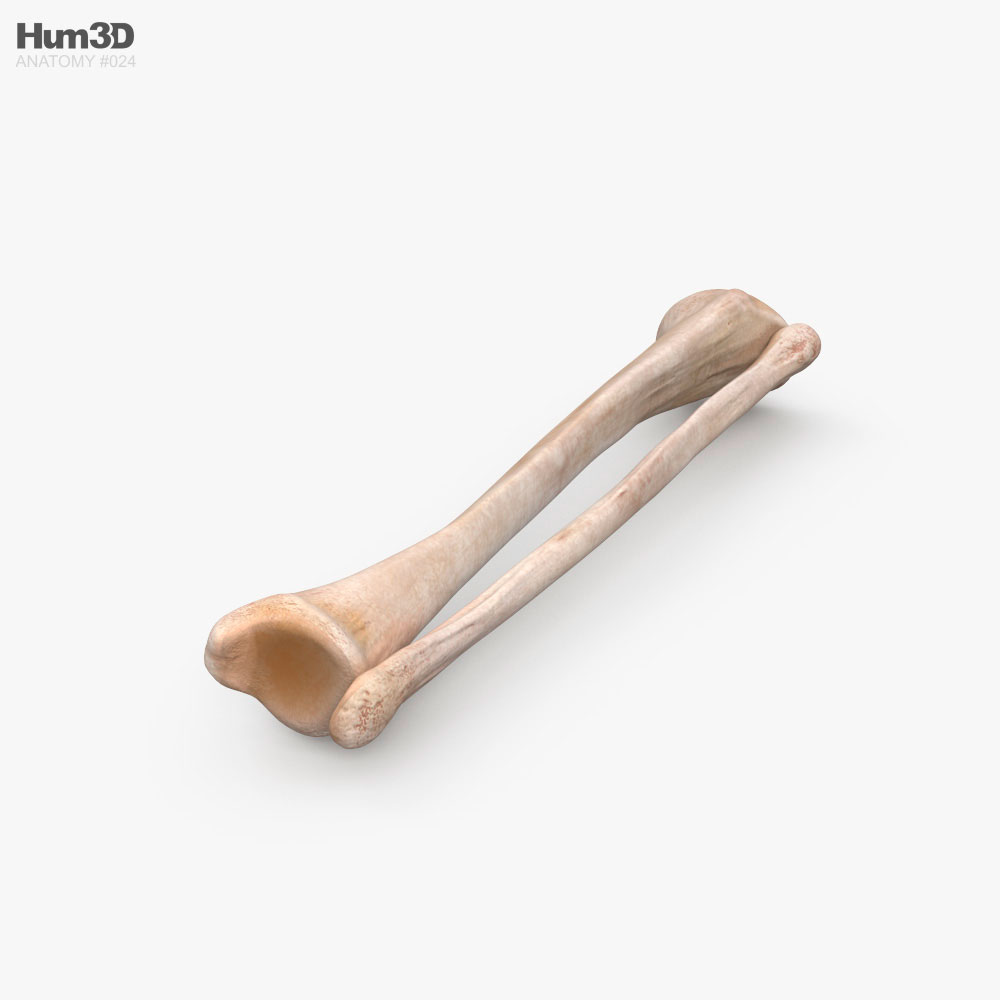

Анатомия фибулы: Подробные фотографии и схемы